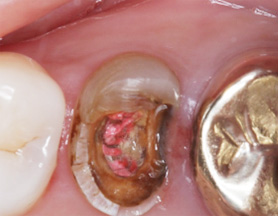

치근단 염증

신경관 소독

신경관 약재삽입

약재주입 후 반응